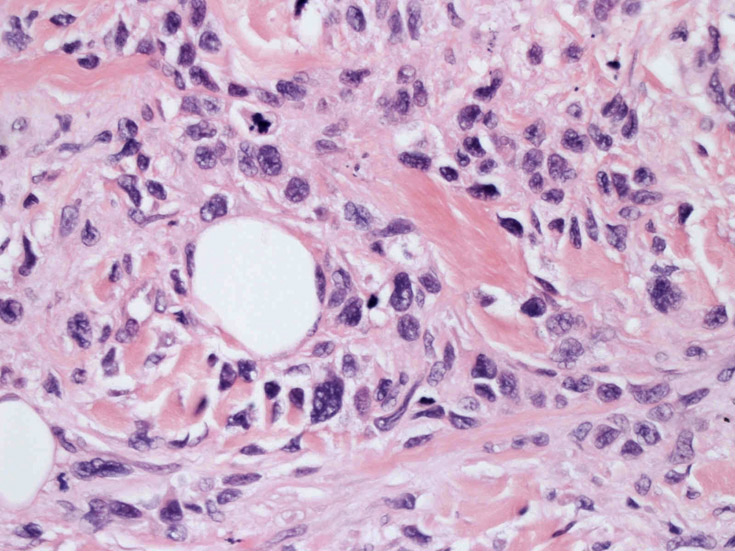

皮膚に異型細胞の浸潤がみられる。異型細胞は表皮内に浸潤するほか、表皮真皮境界部, 真皮, 皮下脂肪組織にもびまん, 結節様の浸潤所見を示す。血管周囲に浸潤、集蔟する所見も多く見られる。 増殖浸潤細胞の核には類円形や腎臓形, またはへこみ, 切れ込み, 溝などを有する多型な核が認められる。クロマチンは粗でvesicularな核が多い。核小体の明らかな核もある。好エオジン性の核内封入体様構造も少数に見られた。mitosisは容易に認められる。hyperchromaticな多型核, bizzarreな細胞が高頻度に認められ異型度は高いと考えられる。細胞質は境界不明瞭, 淡明または泡沫様の 好エオジン性胞体である。

免疫染色 浸潤細胞はCD1a+, S100+, Langerin+, HLA-DR+, CD4+, CD45+, CD68+. MIB-1 index:24.4%